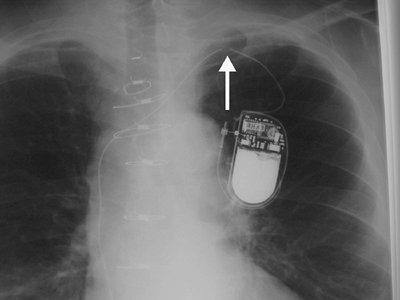

Numerous types of single- and dual-lead pacemakers and combination pacer–defibrillators are available. They are used to treat a variety of dysrhythmias. Accurate interpretation of their appearance on chest radiography requires knowledge of the specific type of pacemaker placed. The three major approaches to insertion of a pacemaker electrode into the heart include epicardial, subxiphoid, and transvenous implantations; transvenous is the most common. With single-lead pacers, the wire is placed into the right ventricle by way of the cephalic, subclavian, or jugular vein. When the lead is wedged into the myocardial trabeculae near the cardiac apex, the lead will be stable and have maximal contact with the endocardial surface. With dual-lead pacers, one lead is generally placed into the right atrium and the other into the right ventricle. It is important to know where the desired placement of leads is for each patient, because placement within the coronary sinus may be accidental or purposeful. After the electrodes are positioned, the generator is placed in a pouch in the subcutaneous tissues of the chest wall or beneath the pectoralis muscle. Biventricular pacemakers are used to treat congestive heart failure. Leads are placed in the right atrium and right ventricle, and a third lead is placed in the coronary sinus for pacing the left ventricle (Fig. 5-18).

Failure of the pacemaker to elicit a ventricular response may be caused by (a) exit block, (b) lead fracture, (c) electrode dislodgment, (d) electrode malposition, (e) myocardial perforation, (f) thrombosis, (g) infection, or (h) battery failure (20). Of these, malpositioning, fracture, and perforation may be recognized on chest radiographs. The leads can be malpositioned within the coronary sinus, and in this case the catheter often appears to be ideally positioned on the frontal radiograph but

P.71

is directed posteriorly rather than anteriorly on the lateral projection. Approximately 2.7% of electrodes will fracture (21), generally near the pulse generator, at sharp bends in the lead wires, at the point of venous entry, or where the lead is embedded in the cardiac muscle (Figs. 5-19, 5-20, 5-21). If the insulating sheath holds the ends of a fractured lead in close proximity, the fracture may not be readily visible on a radiograph. Tight anchoring ligatures at the venous entry site can produce lucency of the lead, giving the false appearance of a fracture.